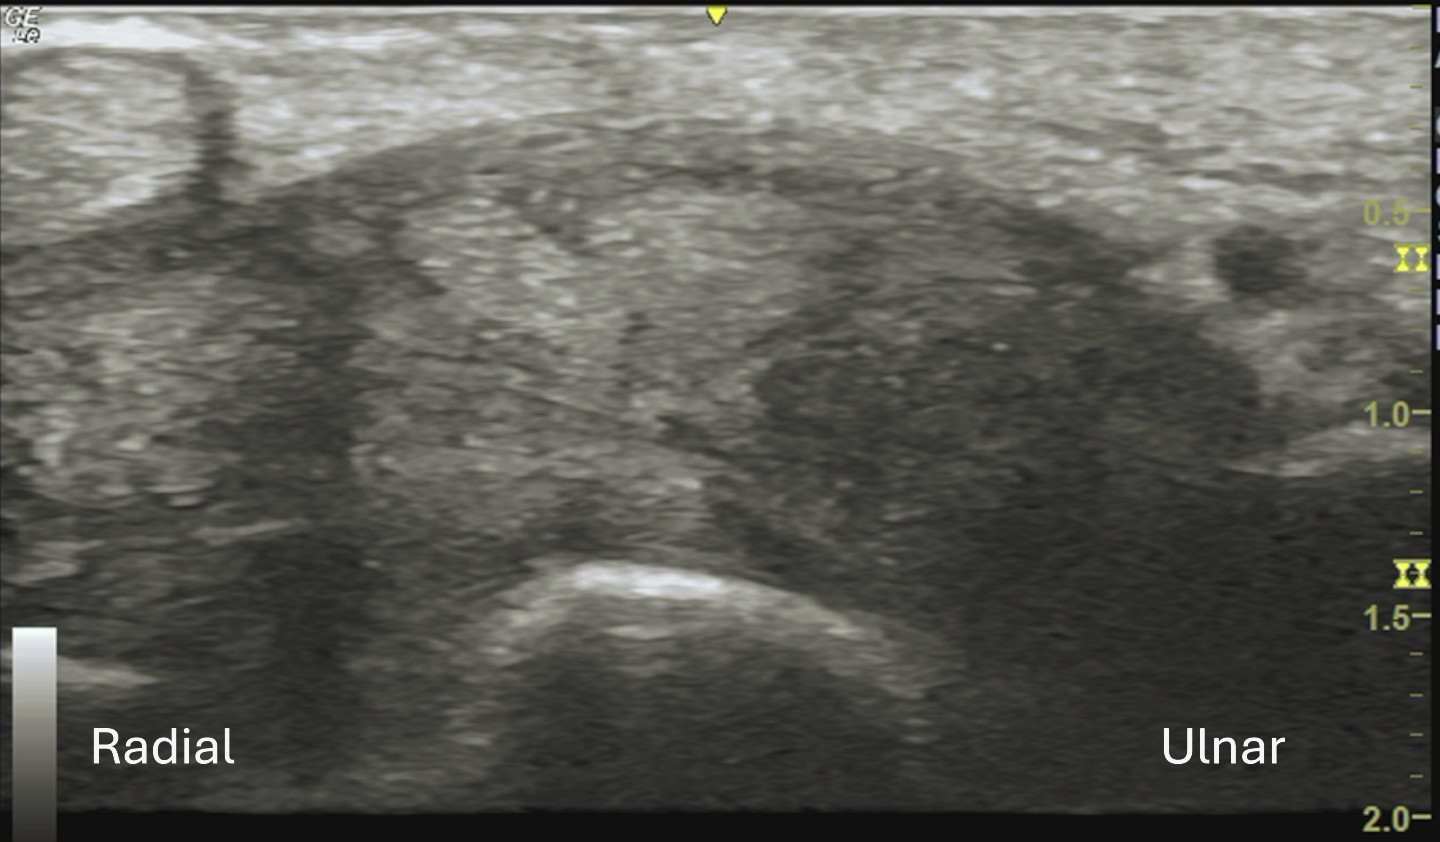

Unlabeled short axis view of the mid carpal tunnel.

Video demonstrates scanning of the median nerve in short axis as it traverses the carpal tunnel from the inlet to the distal portion in a case of carpal syndrome secondary to transthyretin amyloidosis. As the nerve courses distally, there is abrupt tapering and compression within the carpal tunnel, with the median nerve becoming poorly visualized distally. The nerve is surrounded throughout the tunnel by diffuse, homogeneous isoechoic soft tissue.